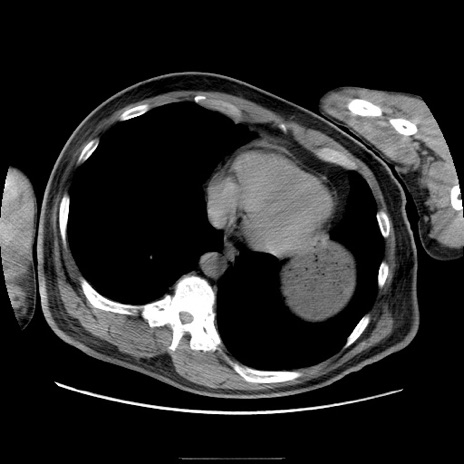

冠状断像

【症例】50歳代男性

【主訴】腹痛

【現病歴】AVMからの被殻出血のため回復期リハ病棟入院中。 本日午後3時頃急に下腹部痛が出現した。

【既往歴】AVM、被殻出血、虫垂炎、高血圧

【身体所見】意識晴明、左半身不全麻痺、会話の理解は良好、36.5°C、腹部:膨隆、全体に板状硬、下腹部正中に圧痛点あり、反跳痛-、筋性防御不明、右下腹部にope scar

【データ】WBC 9400、CRP 0.06